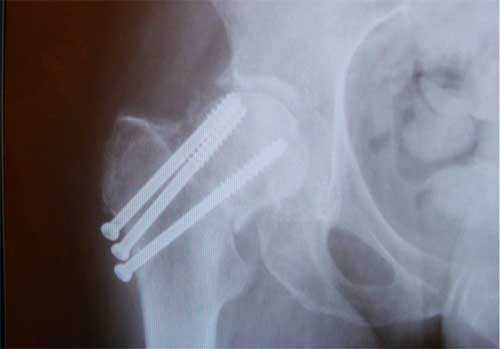

г. перелом шейки на рентгенограмме, д. схематическое изображение остеосинтеза шейки винтами.